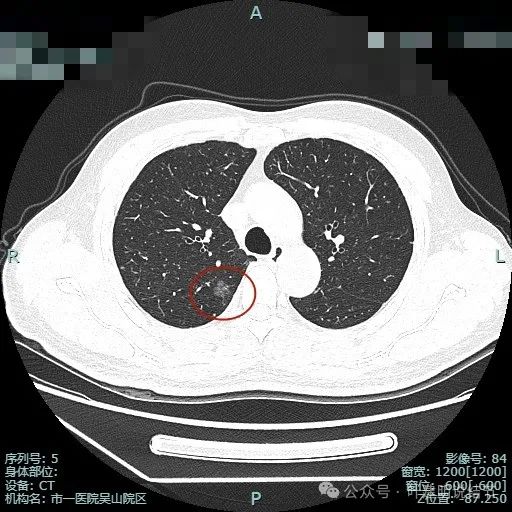

图片

主病灶术前定位,医用胶就在病灶边上(上图绿色的是定位医用胶,红色箭头指的是病灶6)。